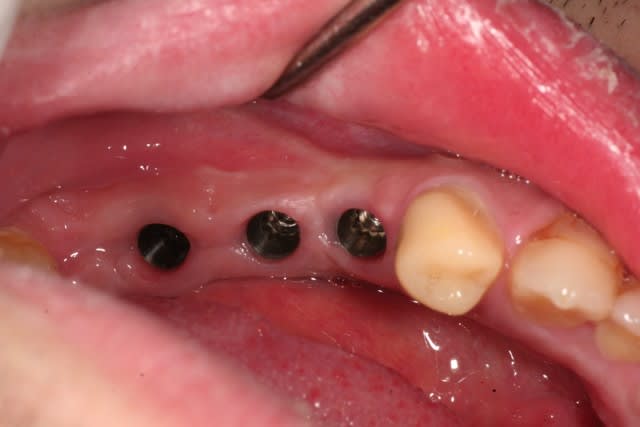

on continue avec ce cas...

ces quelques images ont pour but de dédramatiser la prothèse sur implants, et bien montrer que ce n'est pas pire qu'Ikéa...

pour ceux qui ne sont pas familiers avec ce type de procédure, les questions sont les bienvenues.

est ce que tu solidarises tes transferts entre eux avant l'empreinte ?

tu ne protèges pas tes vis pour devisser plus facilement en pick up avec cire ou autre perso je mets de la cire d'ortho(celle pour éviter les blessures) qu'on enlève très facilement ?http://www.eugenol.com/eugenol/file.php?21,file=14295

quel matériau d'empreinte(DMG) ?

.

non, je ne solidarise pas sur une petite portée comme ça. quand c'est plus grand, je passe à l'empreinte au plâtre.

ici c'est du pentasoft, et si tu regardes bien, les têtes de vis sont accessibles pour le dévissage.